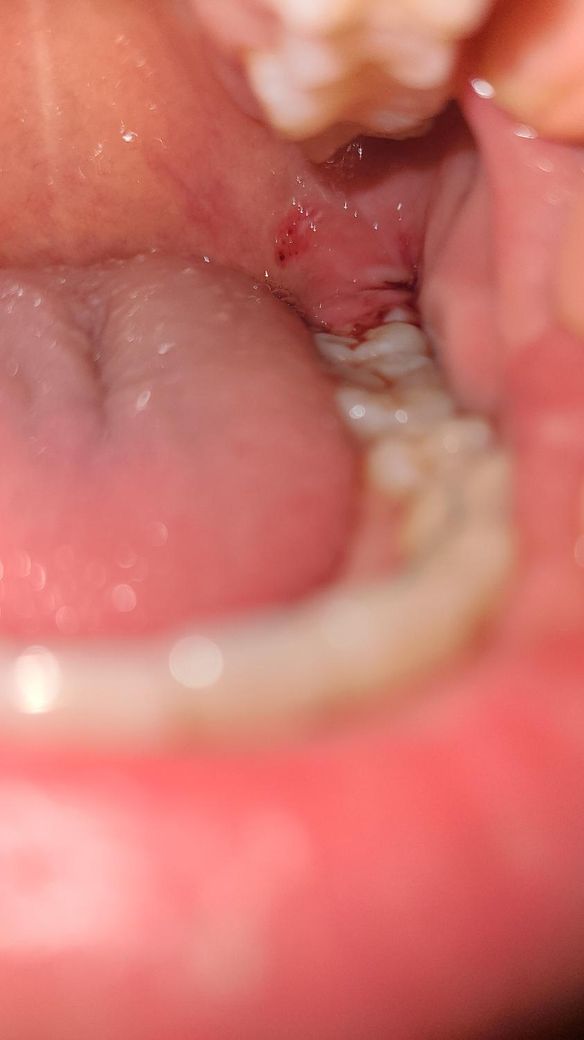

사랑니 발치 후 하루 지난 상태(피떡)

현재 하루 지났는데 간헐적으로 피가 조금씩 났다가 없다가 한 상태입니다 ,, 피떡이 붙어있는건니, 생긴건지 육안으로는 확인하기 어려워서 여쭤봅니다!

현재 정상적으로 잘 아물고 있는 것으로 보이며, 혈병을 억지로 떼어내지 말고 음압이 걸리는 빨대사용은 피하길 권합니다. 묻어나오는 피는 벧지 말고 삼키길 권합니다.

사진상에 보이는 정도면 지혈이 거의 된거 같습니다. 문제가 잇는건 없는거 같으니 음식물이 남지 않도록만 잘 헹궈주세요.

사진상 특별히 문제가 있는 상황은 아닌 것으로 보입니다. 앞으로 발치 후 주의사항 잘 지켜 생활하시고, 처방된 약도 잘 복용하시기 바랍니다.

사진으로 볼때는 크게 문제가 되지는 않을것으로 생각됩니다. 발치된 부위를 자극하지 맣고 출혈이 된다면 거즈를 물고 있는 것이 좋습니다.